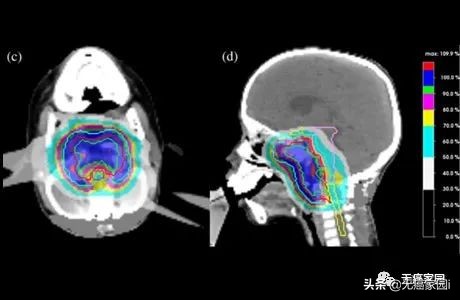

图像取自“点扫描质子放射疗法

质子治疗的更高精确度使健康器官不受影响,允许更高剂量的辐射传递到颅底肿瘤。剂量越高,肿瘤控制得越好。

在目前的情况下,质子治疗能够实现更好的肿瘤覆盖率,大约为99%(规定剂量为72 Gy),而光子治疗为91%。相比之下,质子治疗对脑干的最大剂量为57 Gy,光子治疗计划为63 Gy。质子计划实现的脑干平均剂量为4.8 Gy,显著低于光子治疗的24 Gy。

上图:质子治疗的辐射覆盖范围;没有出口剂量;

下图:光子疗法的辐射覆盖率;存在出口剂量

该患者在8周内接受了40质子放射治疗分数的72Gy的生物等效剂量。没有给予额外的全身治疗。患者对药物的耐受性良好,毒性有限,目前正接受常规随访。

最后对159例颅底软骨肉瘤患者进行的研究证实,全身高剂量辅助质子治疗可实现高局部控制率且毒性最小。低残疾风险,然后进行大剂量质子束治疗,似乎可以在颅底软骨肉瘤中获得最佳的长期效果。